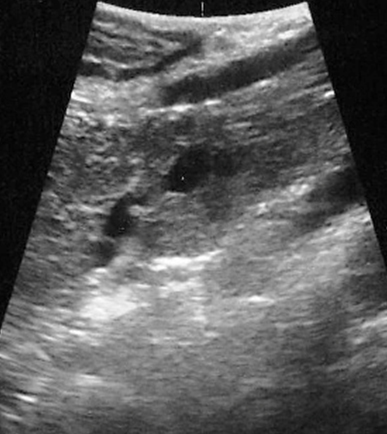

image

Aspetti TC: piccolo nodulo istmico ipervascolarizzato in fase pancreatica